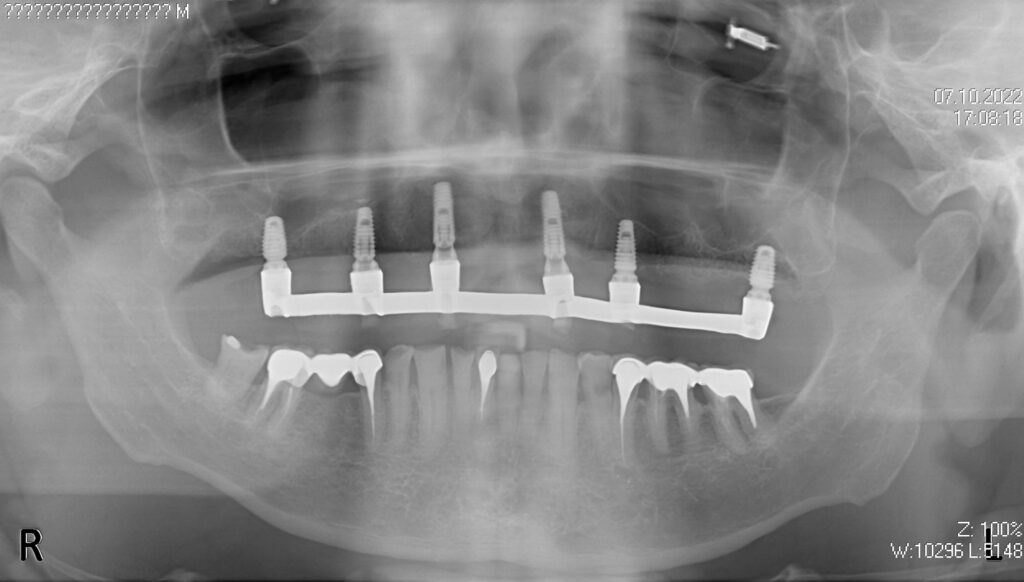

На верхней челюсти были удалены зубы и проведена комплексная имплантация по системе All-on-6,

установлены 6 имплантатов Megagen AnyOne.

Спустя 7 дней на верхней челюсти зафиксирован металлоакриловый протез из 12 зубов.

в процессе имплантации

снимок